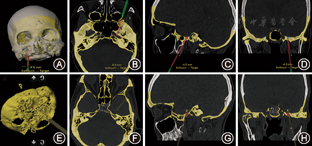

透视组治疗操作采用电生理监测C形臂引导下Hartel前入路选择性三叉神经半月节RFT[4,5]。导航组操作流程如下:(1)术前影像扫描与导航路径规划:术前1 d行头颅三维螺旋CT平扫(德国西门子公司),扫描参数:1 mm,无间距,骨窗位+脑窗位。影像数据以Dicome格式读入神经导航工作站(iCranial v.3.0 stereotacxy,德国BrainLab公司),骨窗位与脑窗位影像进行融合,在骨窗位像轴位、矢状位、冠状位对卵圆孔结构进行描记和平滑处理。在脑组织窗位进行三叉神经半月节描记,以三叉神经半月节为靶点,根据Hartel前入路原则,初步设定皮肤穿刺点,通过轴位断层平面,调整穿刺点及穿刺路径角度,在骨窗位确认穿刺路径经过翼腭窝进入卵圆孔内口且无骨性组织阻挡,测量并记录穿刺路径长度。(2)手术流程:患者取平卧位,导航系统ENT参考架(Kick系列,德国BrainLab公司)固定于前额部,头部略后仰并枕于硅胶头圈。导航屏幕界面及红外摄像头放置术者对侧,并获取ENT参考架反射球位置,以红外注册器扫描面部并通过骨性标记点验证注册准确性后,导航指示笔标记面部穿刺点。随后进入无菌操作阶段,穿刺电极采用Tew射频电极(Cosman公司,美国)[1],将器械参考架固定于穿刺电极顶部,通过"象鼻"模具注册并校准,针尖变异度<0.3 mm,穿刺路径变异<0.3°接受为注册成功。面部穿刺点以1%利多卡因局部麻醉后,根据导航计划量取穿刺路径长度,设定引导界面穿刺针尖轴性延长界面(图1A~D),根据轴位、冠状位、矢状位及3D成像界面,调整器械角度与计划穿刺路径吻合后进行穿刺。穿刺过程适度微调修正进针过程中角度偏移直至进入卵圆孔内口到达靶点(图1)。然后给予电生理刺激验证,拔出穿刺针内芯,先以直尖电极置入穿刺套管,以脉宽2 ms,频率50 Hz(感觉)、2 Hz(运动)的脉冲电流0~1 V进行刺激测试,如诱发出原有三叉神经疼痛区域的感觉异常或疼痛,则直接进行射频热凝治疗,否则更换弯尖内芯进行刺激位置调整,直至诱发的疼痛及面肌运动的区域与受累三叉神经分支的分布区域相吻合。以静脉持续泵注芬太尼(25~50 μg/5~10 min)或咪达唑仑(1~2 mg/5~10 min)进行镇静镇痛,镇静程度以能轻易呼唤清醒及准确应答为宜(Richmond躁动镇静评分-1分)。采用G4射频仪(Cosman公司,美国)进行温控射频65~80 ℃逐渐升温,4~6次循环(60~90 s),并逐渐调整射频针尖深度,整个过程共约5~6 min,并每循环测试面部痛觉诱发及感觉改变情况,直至多次触碰"扳机点"未诱发疼痛发作为止。